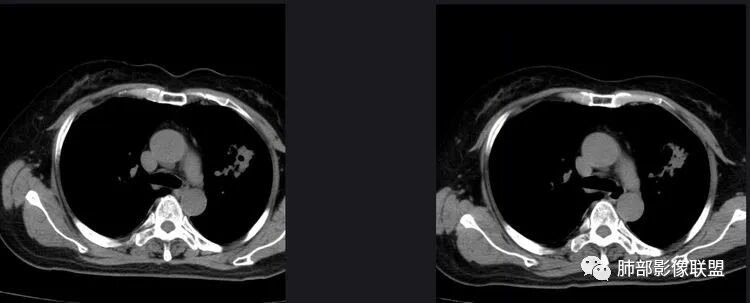

以下是两个时间点左右对比

2019.11.26  👇                           2020.01.20👇                                            2019.11.26片

2020.01.20片

1.老年女性,咳嗽咳痰一月,伴咯血及痰中带血,多为咳白痰,无发热,炎性指标不高,且抗炎治疗,两月后病灶未见明显吸收和改变,普通病原体感染不支持。

2.早期CT表现左肺上叶不规则团块影,呈混合密度,以实性密度为主,但整体密度偏低,周围隐约见磨玻璃密度影。

边缘不规则,前内侧缘见小叶间隔限制(注意,并非典型深分叶),病灶外侧细长毛刺,病灶内有小空泡及空气支气管征,有胸膜牵拉征象。

上述征象均提示病灶为恶性病灶,但边缘特征及空气支气管征似乎有别于常见的浸润性腺癌及MALT。

3.复查影像显示病灶整体大小变化不明显,其内空泡消失,但是周围磨玻璃影趋于似清非清,整体病灶收缩力中等偏弱,均提示粘液腺癌的可能性大。